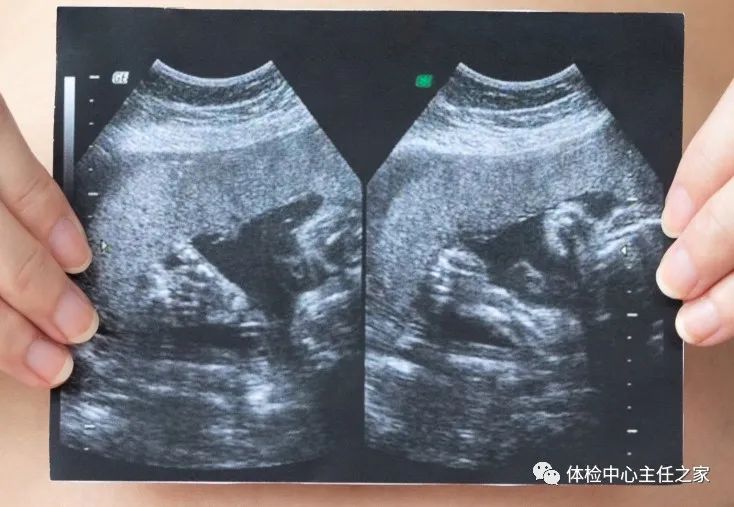

B超的原理是用超声波穿透人体,当声波遇到人体组织时会产生反射波,通过计算反射波成像。就像挑西瓜一样,边敲边看病灶显示情况。B超在胆囊疾病的诊断上,如胆囊结石,有高度准确性,一般准确率在95%以上。

B超检查是临床上检查胆道疾病最常用的方法,可确诊胆囊结石、胆囊炎症和肿瘤等,而且B超对肝硬化、脂肪肝、脾肿大、肝癌和肠道占位性病变准确率也较高。

除肠道外,一般超声都能检查

腹腔器官受呼吸影响较大,进而影响到CT和MRI成像,而超声不会因此受影响。同时,超声对肝脏、脾脏、胰腺、肾脏和盆腔等诊断准确率较高。但是超声受气体干扰很大,对于肠道等含气较多的器官,超声诊断准确率会降低。